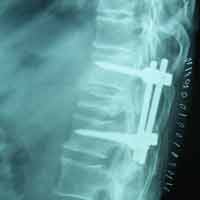

Pre-op Lateral

60 years old female with one& half months old fracture L1 presented with complete paraplegia with bladder & bowel involvement. She was treated with posterior decompression (Laminectomy), reduction of retroplused fragrant & pedicure screw fixation. Full neurological recovery on 6th day.

Case:1 Traumatic Fracture L1 with Cauda Equina